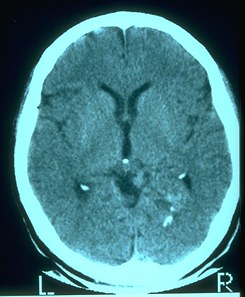

[Cat

Scan Hemorrhage]  [Cat

Scan Tumor]  CT (Computerized Tomography): 3-dimensional low energy x-ray scans of brain processed by computer